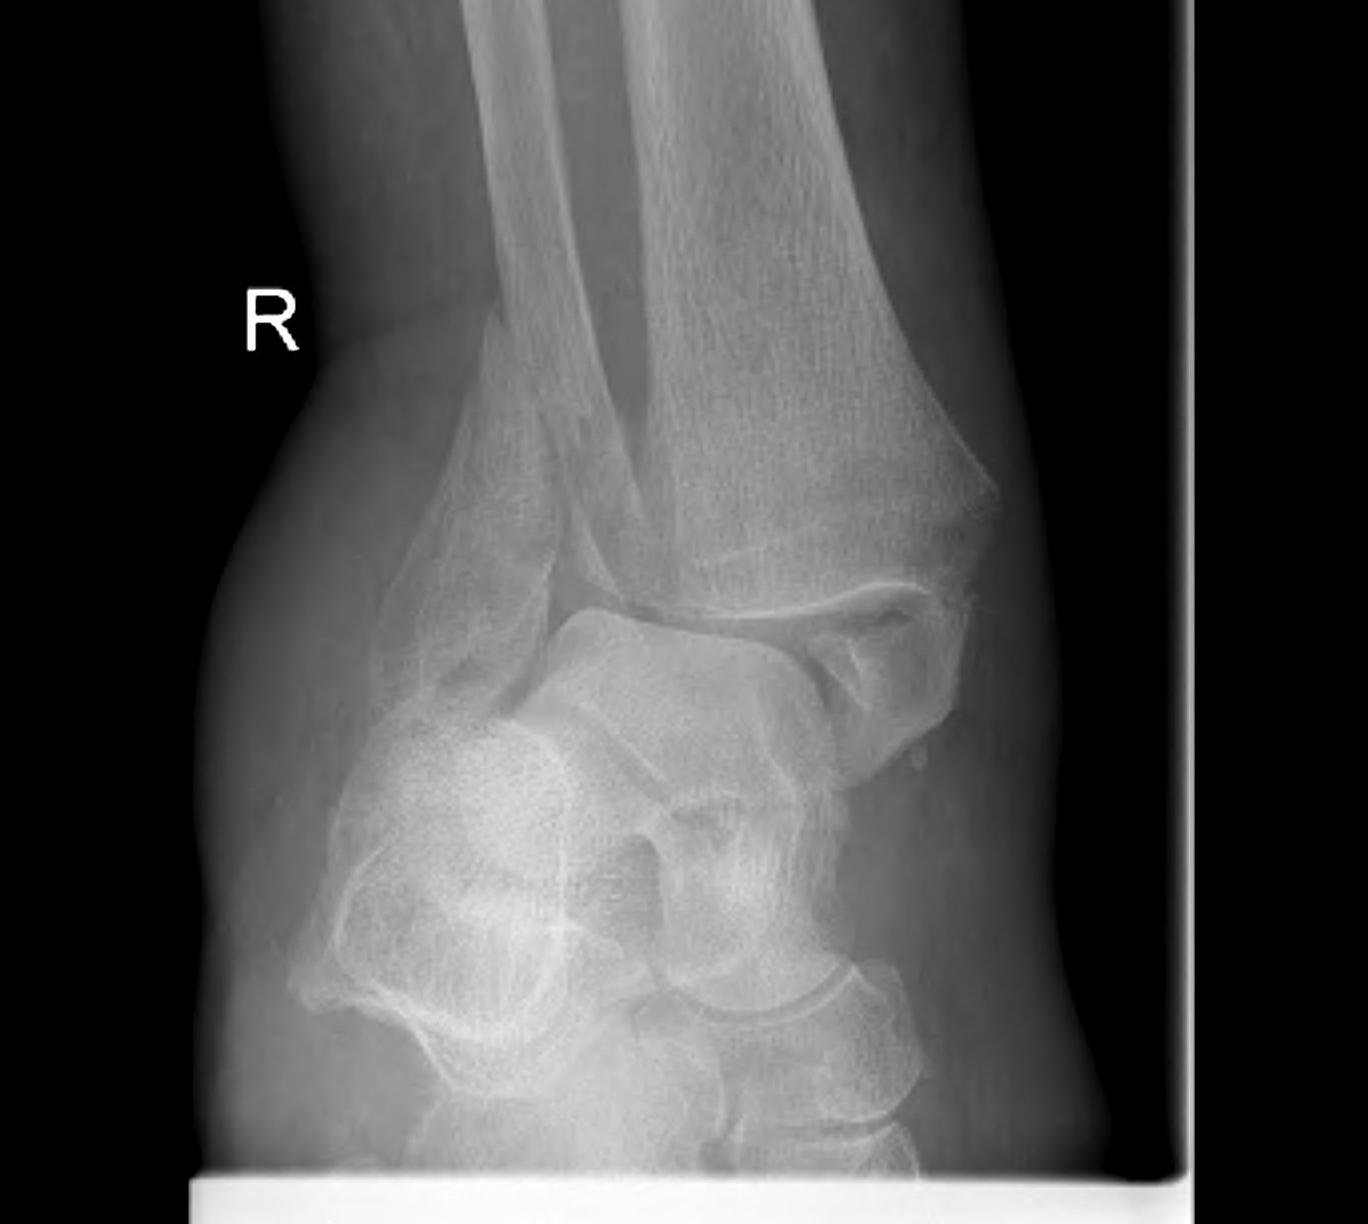

Fracture patterns

| Lateral malleolar fractures | Medial malleolar fractures | Bimalleolar fractures | Trimalleolar fractures |

Weber A - below syndesmosis Weber B - at syndesmosis Weber C - above syndesmosis |

Uncommon |

Fibular + medial malleolus Bimalleolar equivalent - fibular + deltoid ligament Fibular + posterior malleolus |

Fibular fracture + Medial malleolus fracture + Posterior malleolus fracture |